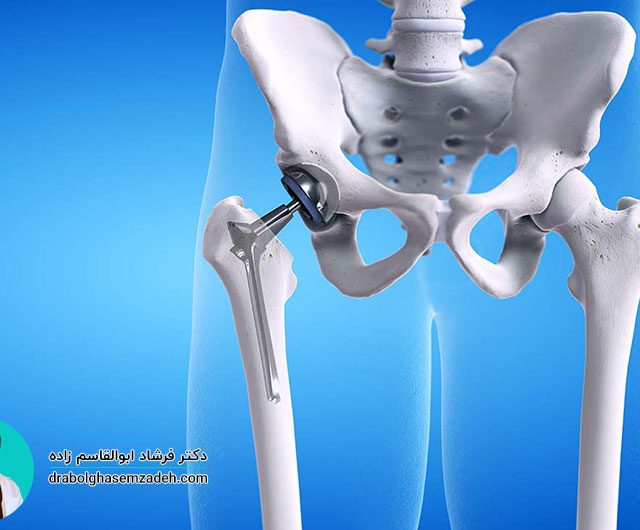

علت درد بازو

بیشتر افراد به هنگام داشتن بازو درد، علت آن را وارد شدن ضربه به آن می دانند. وارد شدن ضربه به بازو، یکی از دلایل درد بازو عنوان شده است؛ اما دلایل دیگری برای احساس درد در بازوها وجود دارند. برای درمان، درد بازو، مهم ترین کار تشخیص علت درد بازو است. علت درد، انتخاب […]...